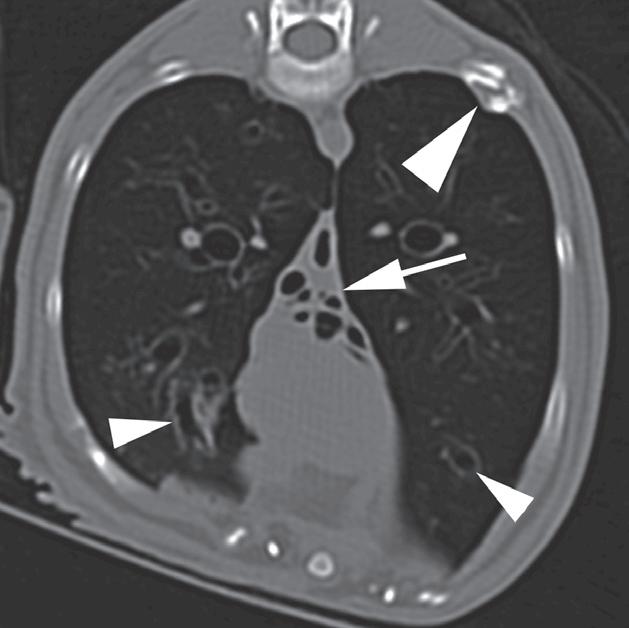

Rycina 4.6.4. Kardiogenny obrzęk płucny (kot) TK

Badanie wykonano u 4-letniej, kastrowanej samicy kota domowego krótkowłosego dializowanej z powodu niewydolności nerek. U pacjentki obserwowano echokardiograficzne objawy łagodnej kardiomiopatii. W momencie wykonywania tomografii komputerowej kot był umiarkowanie przeciążony płynami. Obraz na ryc. a jest reprezentatywnym obrazem na poziomie tylnej części klatki piersiowej, a obrazy przedstawione na ryc. b i c stanowią powiększenie ryc. a. Niewielka objętość płynu opłucnowego unosi powietrzne płuco (a – czarna strzałka). Widoczny jest łagodny, rozproszony wzrost atenuacji płuc z dodatkowymi, licznymi zmianami w typie matowej szyby. Wydaje się, że te ostatnie nacieki są najbardziej widoczne wokół naczyń płucnych (a–c – białe strzałki). Badanie pośmiertne potwierdziło, że nacieki były spowodowane obrzękiem płuc. W tym przypadku obrzęk prawdopodobnie był wynikiem względnej niewydolności komór serca spowodowanej kardiomiopatią i przeciążeniem płynami